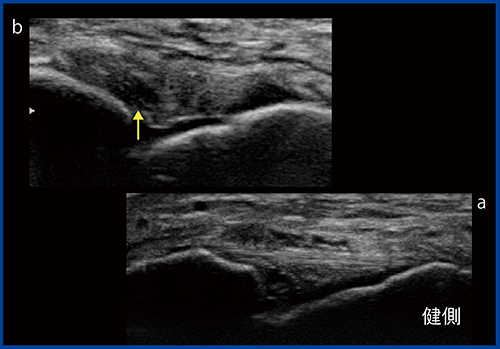

そこで,当院では軟部組織の観察に超音波診断装置を積極的に使用している。例えば捻挫では,足の外側にある前距腓靱帯が損傷する。超音波検査では,前距腓靱帯は腓骨と距骨をつなぐ2〜3mm程度の線状高エコーとして描出されるが(図1a),断裂すると靱帯が腫大し,Bモードで明瞭に観察できる(図1b)。また,靱帯や腱などは動きのある臓器のため,負荷をかけてBモードで観察することで,損傷の状態や,骨との位置関係などを動的に診断することが可能である。

図1 前距腓靱帯のBモード画像

a:正常では2〜3mm程度の線状高エコーとして描出される。

b:断裂すると靱帯が腫大する(↑)。